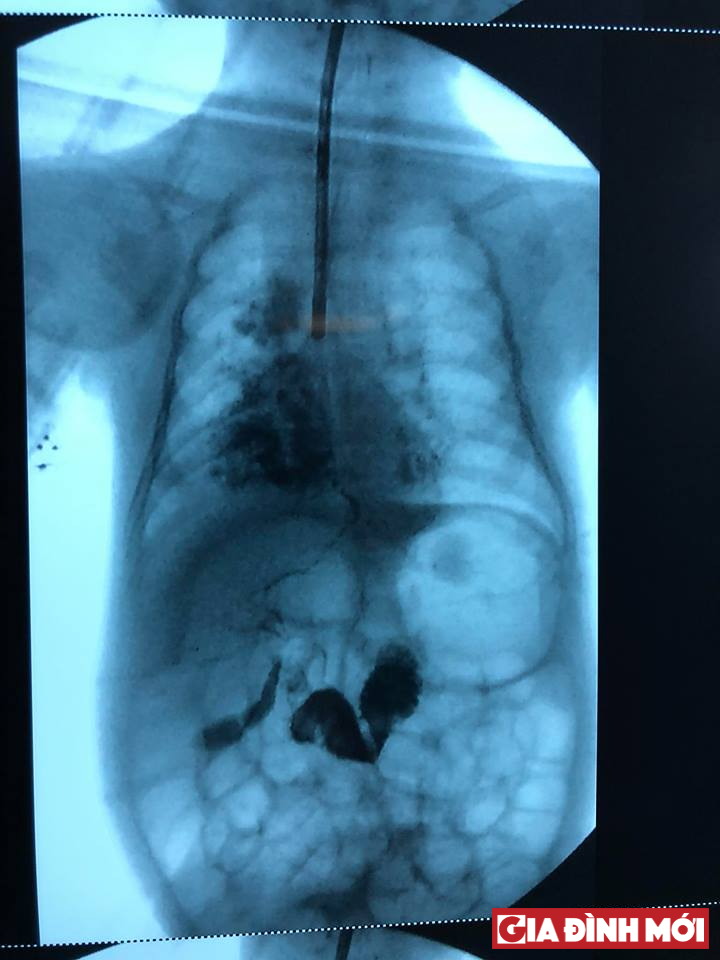

Hình ảnh đường rò gây ra bệnh lý viêm phổi của bé. Ảnh: Gia đình mới |

Bác sĩ cũng chụp Xquang cản quang trong lúc mổ cho thấy đường rò lúc mổ cho hình ảnh của đường mật trong gan và thuốc cản quang xuống tá tràng, không phát hiện dị tật đường mật khác đi kèm.

Sau khi nhập viện, bé gái tiếp tục được điều trị viêm phổi. Tuy nhiên, khi chụp CT scan ngực, kết quả cho thấy bé có một đường rò đường mật từ gan trái vào khí quản, các bác sĩ khoa hô hấp quyết định nội soi khí quản. Nội soi khí quản cho hình ảnh mật chảy vào khí quản nơi phân chia hai phế quản trái và phải.

Trong quá trình phẫu thuật, bác sĩ cho biết, bé có đường rò khá dài từ nơi chia đôi phế quản trái và phải xuyên qua cơ hoành đến gan, nằm cạnh bên thực quản và mạch máu, thần kinh vùng ngực.